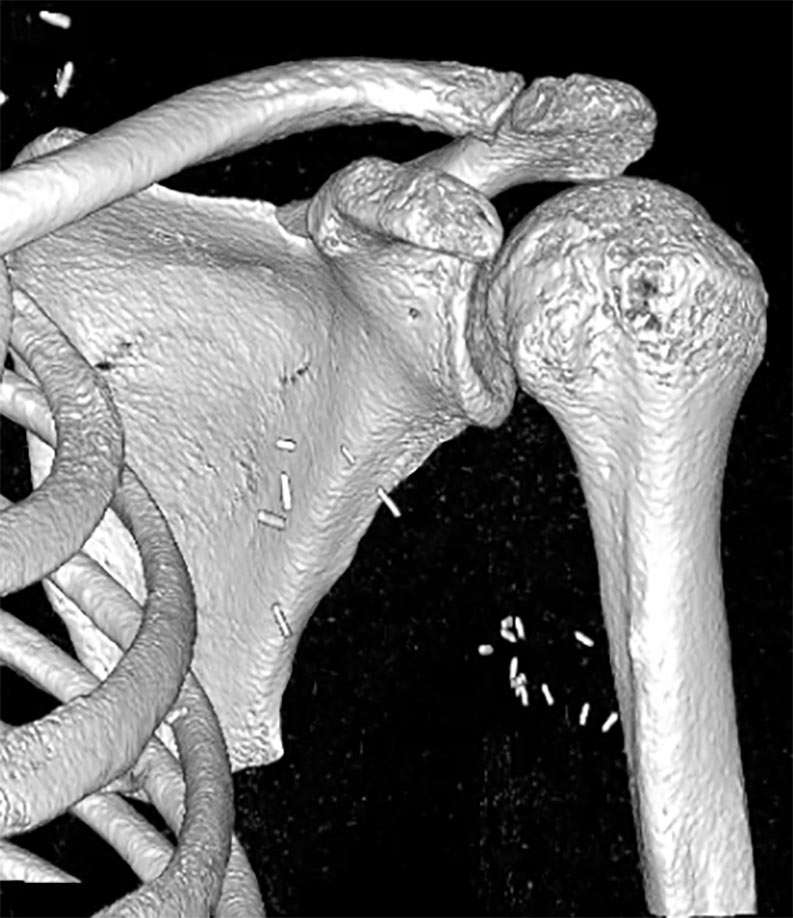

• 09/2023: Motorcycle accident → Brachial plexus injury (C5–C7)

• 3. BUT no glenohumeral active mobility and stability → NON-functional shoulder → Impossible use of the hand

Constant: 21